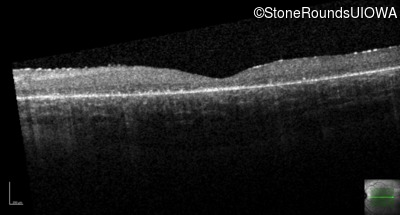

Age at visit: 7 years

OD OS

This 7 year old boy's mother first noticed that he was tripping over objects in dim light about one year ago.